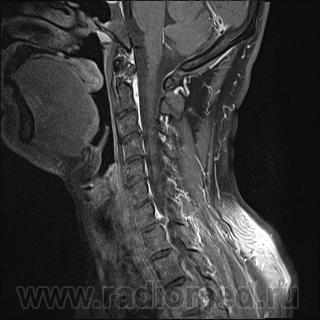

Грыжа диска. А где аксиалы?

Шейный остеохондроз.Грыжа С7-Th1.Не исключено наличие миелопатии на этом уровне, но боюсь ошибиться-изображения мелковаты ,идаже кажется, что есть повышение МРС от спинного мозга по Т1( скорее всего-артефакты?).

Левосторонняя парамедианная с компрессией корешка.

а это не перидурит??? смотрели месяц назад (в начале заболевания) было меньше.

Посмотрите на STIRе. Если жидкости нет, то простая грыжа. На этих сканах вообще-то жидкости не видно. За месяц грыжа могла и подрасти, смотря как лечили.

По-моему, только грыжа.